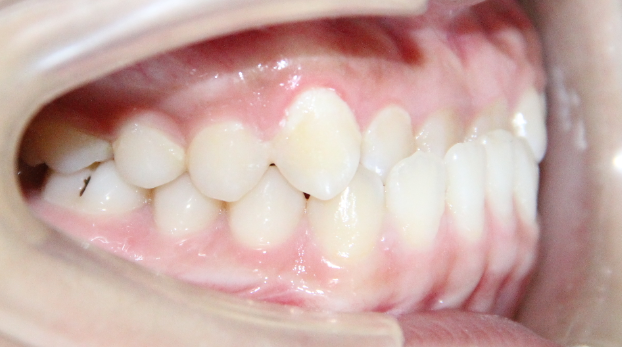

病例1

治疗前